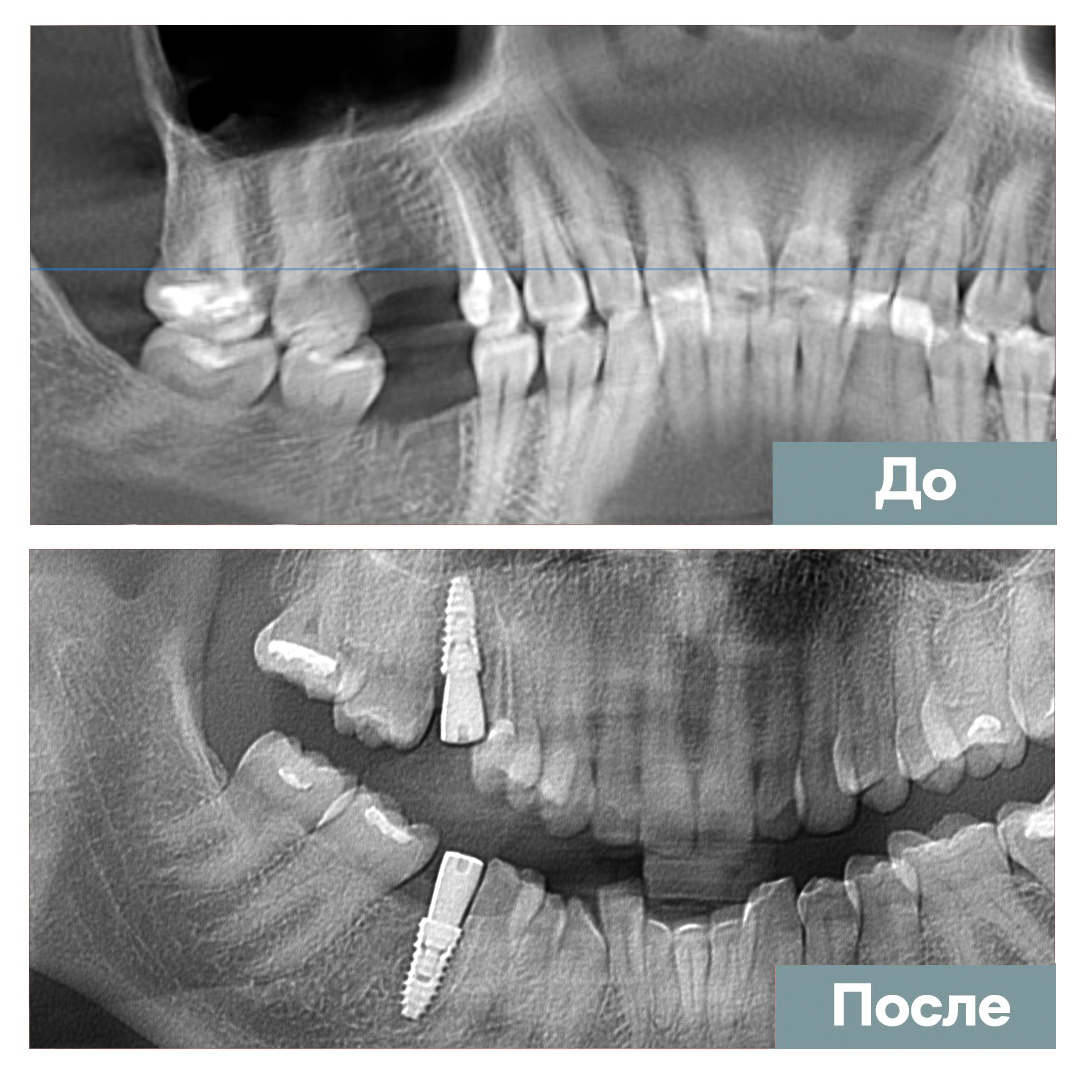

Имплантация 2 ед.

Мазанов